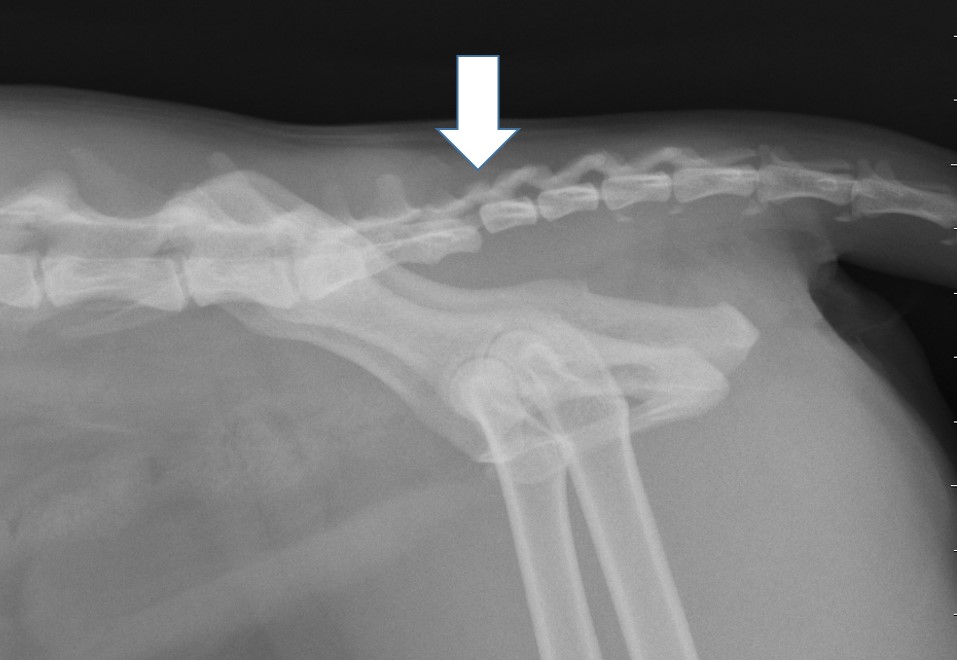

At our hospital we see cat patients after sustaining a trauma. They can have spinal fractures (Fig 1). But because cats have normally a very elastic body, they bend the spine during the trauma until the disk ruptures with a traumatic disk extrusion as consequence. The damage to the spinal cord can be severe, but in most cases a surgery would not help. The MRI is the only diagnostic tool to clearly diagnose such a traumatic extrusion (Fig 2). Fractures to the sacrum and the first vertebra of the tail are also typical for cats. The nerves to the bladder are often damaged in these patients, so the cat has to be in the hospital to ensure the treatment of bladder and fracture (Fig 3).

Fig 1 Fig 2

Fig 1 Fig 2